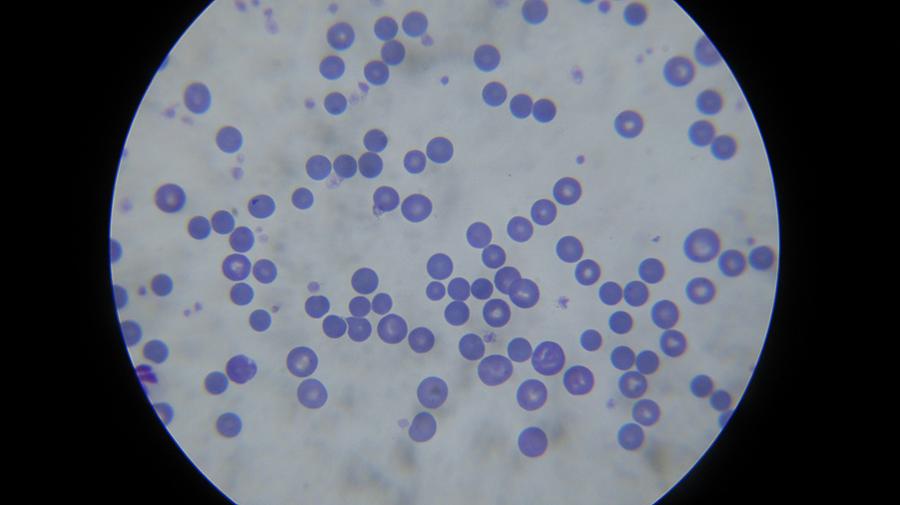

Εργαστηριακές εξετάσεις (αίματος, βιοχημικές, ανοσολογικές, ορμονολογικές, μοριακές τεχνικές)

Εργαστηριακές εξετάσεις

(αίματος, βιοχημικές, ανοσολογικές, ορμονολογικές,

μοριακές τεχνικές)

Το κτηνιατρείο hm vets αναλαμβάνει ψηφιακή ακτινογραφία, έλεγχο δυσπλασίας ισχίου, ορθοπεδική-νευροχειρουργική, χειρουργική μαλακών μορίων, οφθαλμολογία, εσωτερική παθολογία και εργαστηριακές εξετάσεις (αίματος, βιοχημικές, ανοσολογικές, ορμονολογικες, μοριακές και ιστοπαθολογικές).

Το κτηνιατρείο hm vets αναλαμβάνει ψηφιακή ακτινογραφία, έλεγχο δυσπλασίας ισχίου, ορθοπεδική-νευροχειρουργική, χειρουργική μαλακών μορίων, οφθαλμολογία, εσωτερική παθολογία και εργαστηριακές εξετάσεις (αίματος, βιοχημικές, ανοσολογικές, ορμονολογικες, μοριακές και ιστοπαθολογικές).